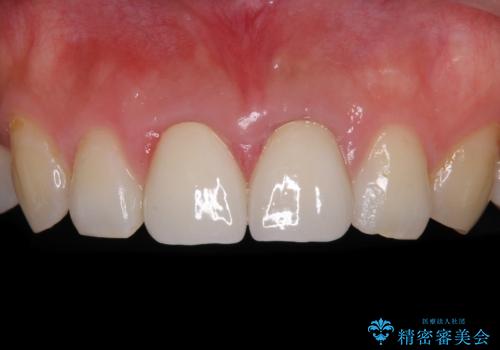

下顎前歯の部分矯正に半年ほどかかってしまい、少し期間は長いものとなりましたが、上下ともに前歯がきれいに整い、患者様には大変満足していただきました。